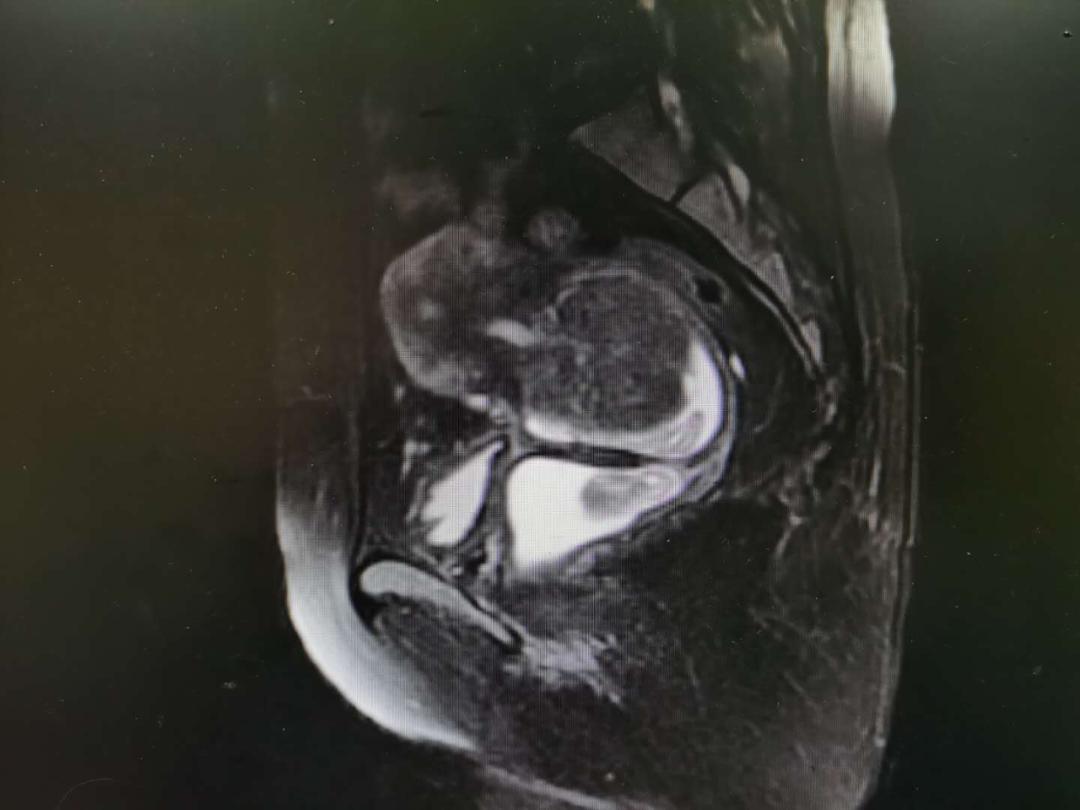

入院盆腔MRI:T1WI、T2WI、DWI及增强扫描子宫前倾位,明显增大变形,子宫内膜信号欠均,未见DWI高信号,左侧壁见大小约2.5×1.5×2.5cm结节,宫颈区见大小约6.3×6.4×7.1cm,T1WI呈等信号,T2WI呈稍低信号,DWI未见弥散受限,增强扫描不均匀强化,其旁见团块状异常信号灶,增强后未见明显强化。右侧附件区见大小约1.5×2.5×2.5cm长T1WI长T2WI信号影,增强后未见强化。盆腔淋巴结未见明显肿大。诊断结果:宫颈肌瘤;子宫左侧壁肌瘤;阴道积血;右侧附件区囊性灶,囊肿考虑;子宫内膜信号欠均,请结合临床。